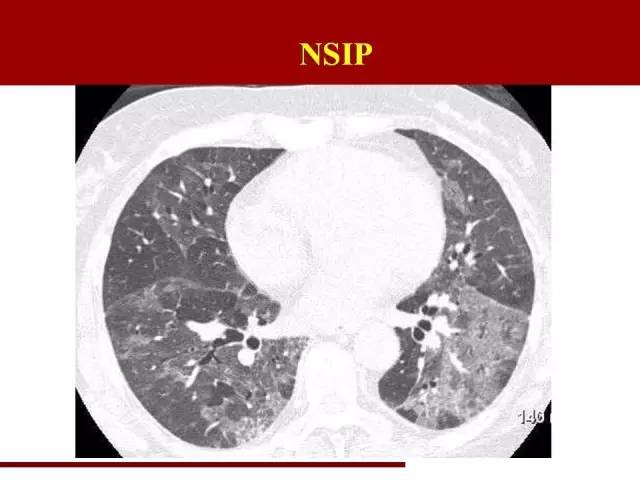

NSIP诊断条件相对放松一些

分布和UIP一致,不同的是磨玻璃阴影多于网格状阴影,可以伴有牵拉性支气管扩张

间质性肺炎的磨玻璃阴影:病理基础为小叶内间质增厚,即肺泡表面的间质发生炎症,覆盖部分肺泡,使肺泡密度增高,形成磨玻璃阴影。在NSIP中,这部分磨玻璃阴影代表着可逆部分,也就是说及时治疗有可能能恢复肺泡功能。因此影像科在报告的时候尽量能把磨玻璃阴影提出来,以便临床进行疾病严重程度评估。

这是NSIP

磨玻璃影比较明显,有可能可以可逆,这部分肺组织的保护很重要

影像科对间质性肺炎的分类的意义大致在此吧